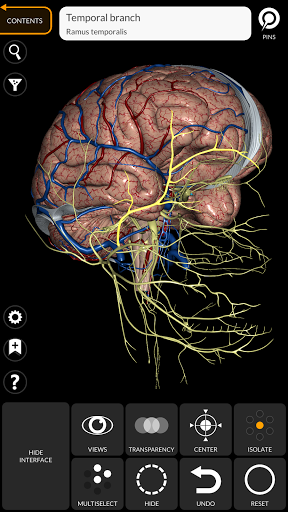

"Anatomía - Atlas 3D" permite estudiar la anatomía humana de forma fácil e interactiva.

A través de una interfaz sencilla e intuitiva es posible observar cada estructura anatómica desde cualquier ángulo.

Los modelos anatómicos 3D son especialmente detallados y con texturas de hasta una resolución de 4k.

La subdivisión por regiones y las vistas predefinidas facilitan la observación y el estudio de partes individuales o grupos de sistemas y las relaciones entre los diferentes órganos.

MODELOS ANATÓMICOS 3D

nervioso • Sistema respiratorio • Sistema digestivo • Sistema urogenital (masculino y femenino) • Sistema endocrino • Sistema linfático • Sistema ocular y auditivo CARACTERÍSTICAS • Interfaz sencilla e intuitiva • Rotar y hacer zoom en cada modelo en el espacio 3D • Opción para ocultar o aislar uno o varios modelos seleccionados • Filtro para ocultar o mostrar cada sistema • Función de búsqueda para encontrar fácilmente cada parte anatómica • Función de marcador para guardar vistas personalizadas • Rotación inteligente que mueve el centro de rotación automáticamente • Función de transparencia • Visualización de músculos a través de niveles de capas desde las superficiales hasta las más profundas • Al seleccionar un modelo o un pin, aparece el término anatómico relacionado • Descripción de los músculos: origen, inserción, inervación y acción • Mostrar/ocultar interfaz de usuario (muy útil con pantallas pequeñas) MULTILINGÜE • Los términos anatómicos y la interfaz de usuario están disponibles en 11 idiomas: latín, inglés, francés, alemán, italiano, portugués, turco, ruso, español, Chino, japonés y coreano • Los términos anatómicos se pueden mostrar en dos idiomas simultáneamente REQUISITOS DEL SISTEMA • Android 8.0 o posterior, dispositivos con al menos 3 GB de RAM Reversi

• Sistema nervioso